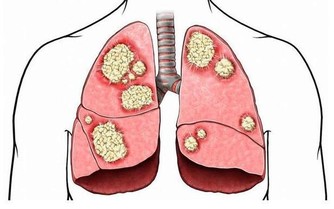

⑵胸椎:比較不會有退化的現象,如有胸椎疼痛,必須懷疑可能是其他疾病,例如心絞痛、膽囊炎、肺膜炎等。